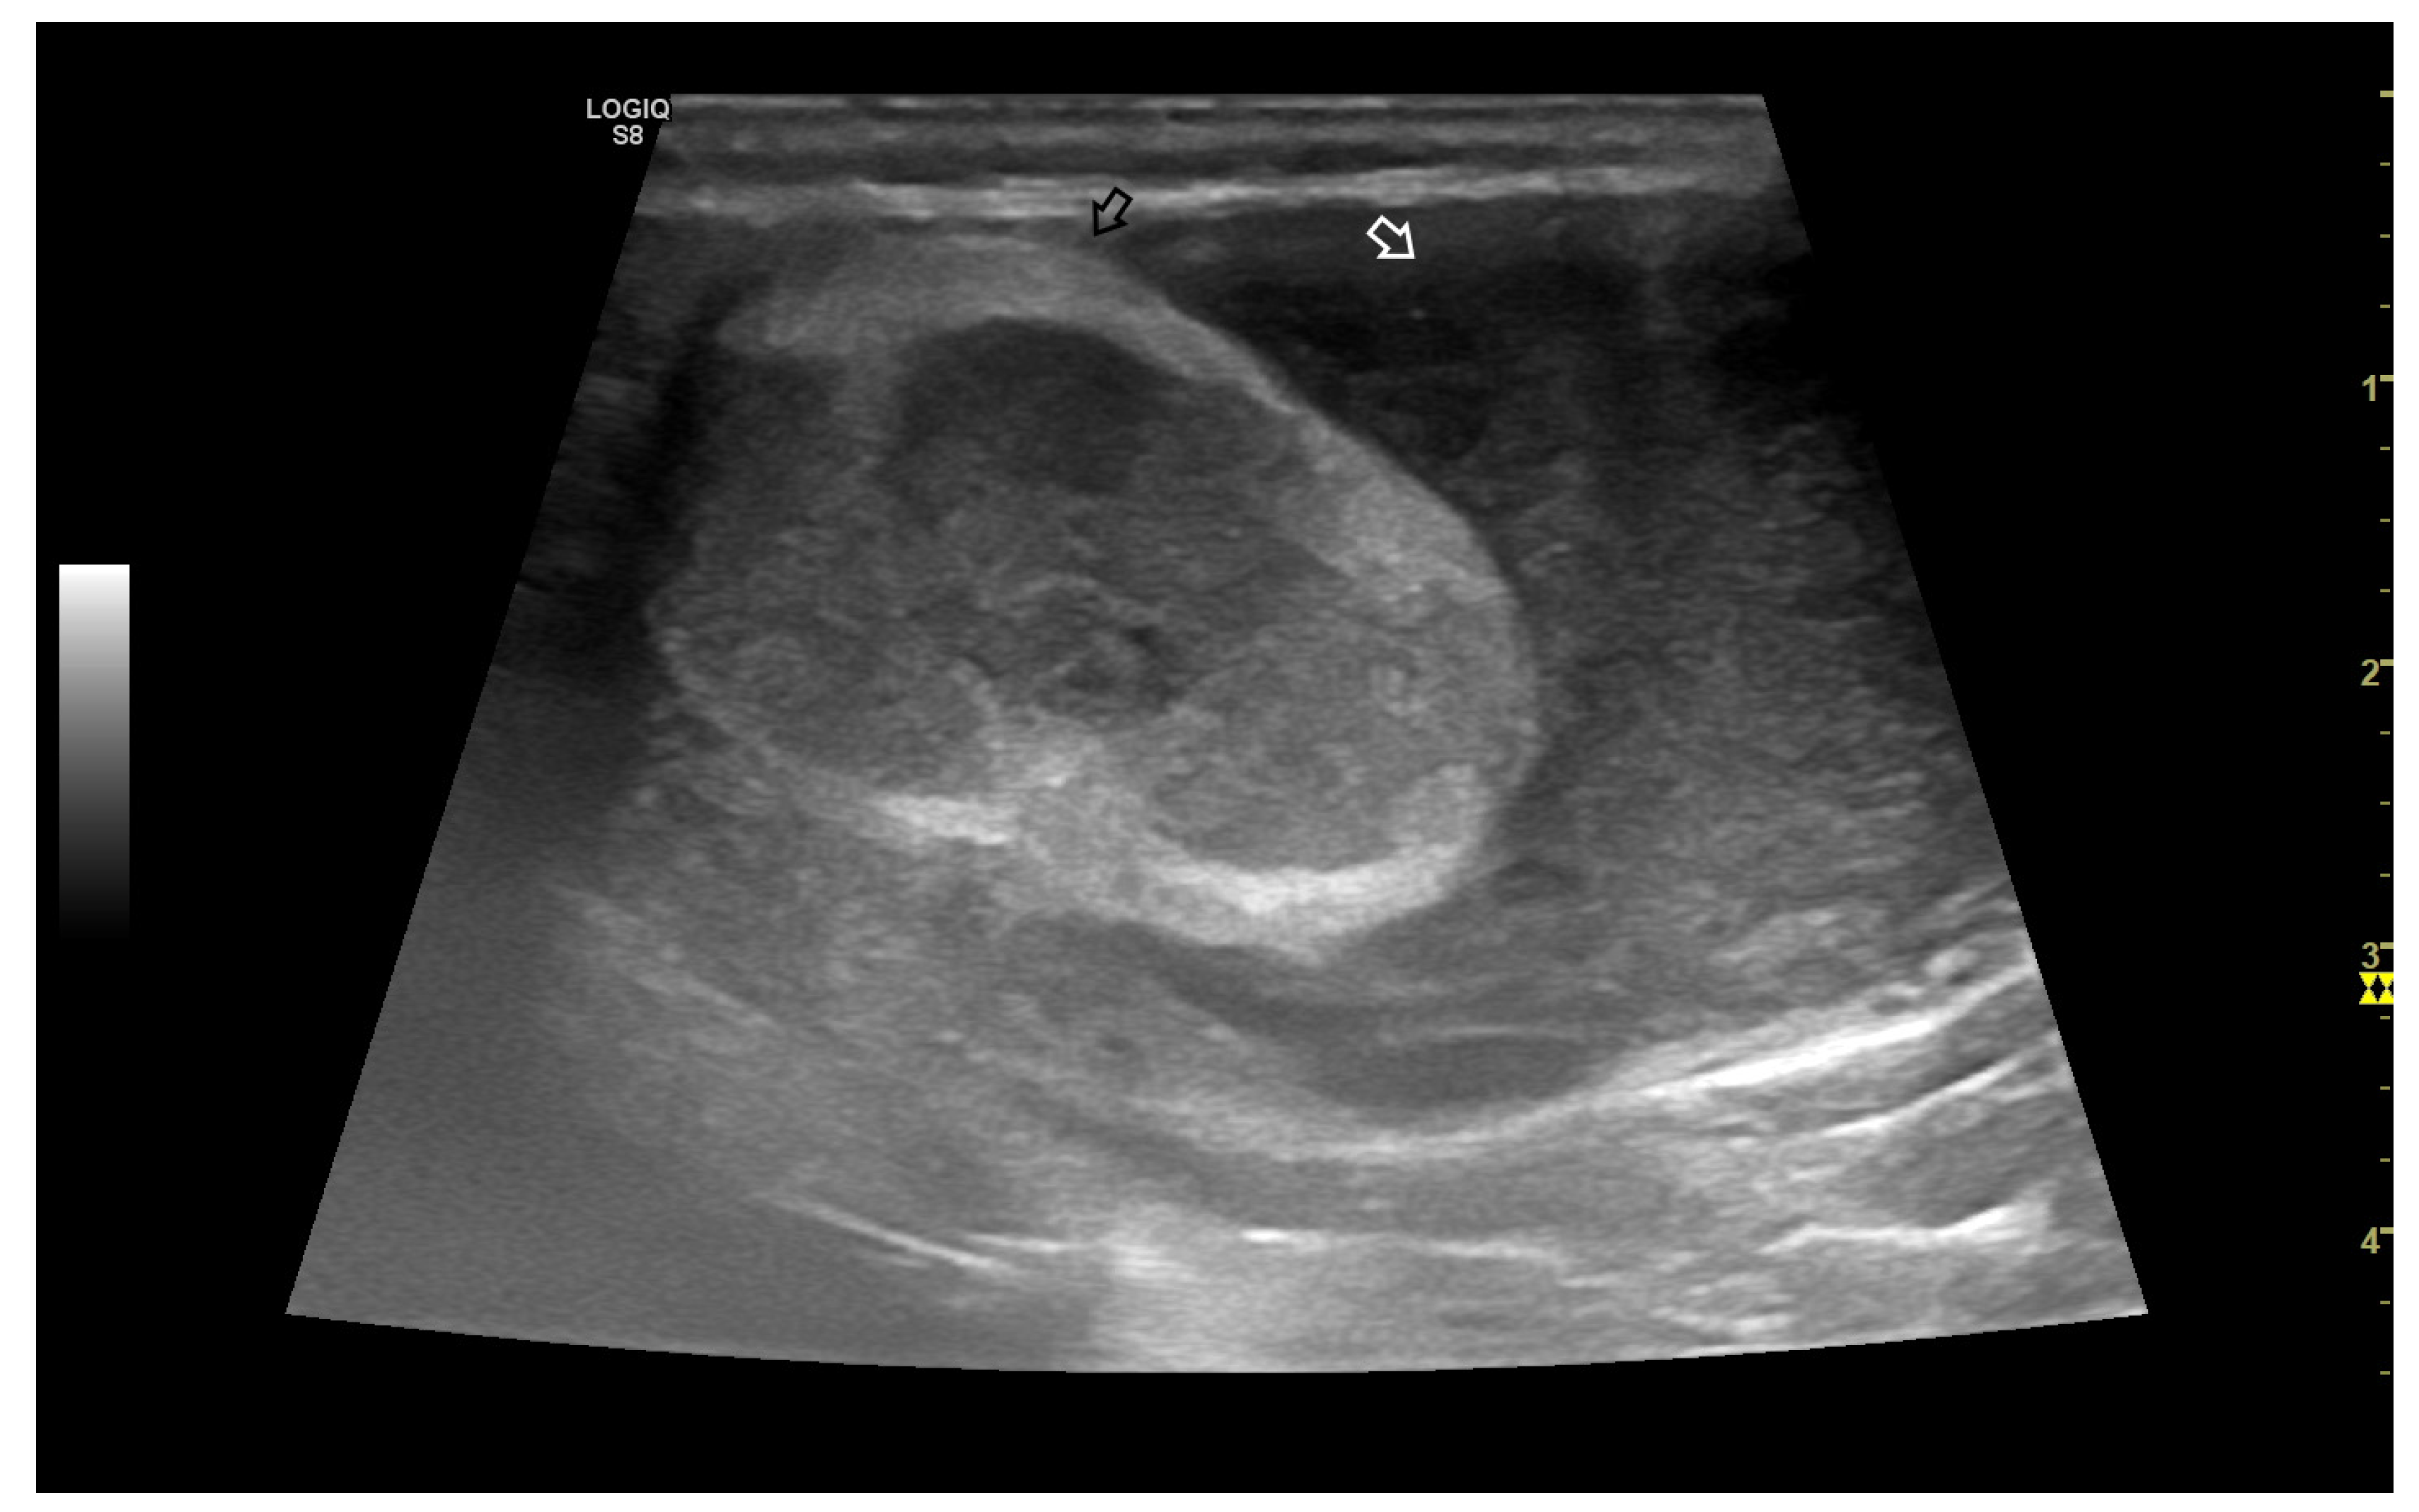

3.4.1. Intratesticular Diseases

3.4.2. Extratesticular Diseases